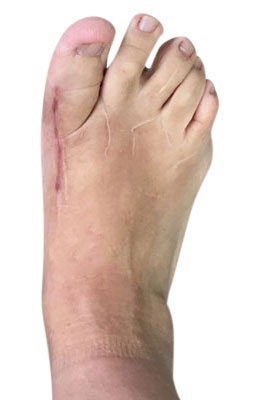

Before

Minimally Invasive Bunion Surgery before

After

Minimally Invasive Bunion Surgery after

Minimally Invasive Bunion Surgery featuring the miniBunon™ System and Tailors Bunionectomy

Melissa is a 32-year-old businesswoman who could not be off her foot post-surgery, yet she had a severely painful bunion. We performed our miniBunon™ System (our trademarked minimally invasive bunion surgery) and had a dramatic correction with no downtime. Melissa continued to work after her bunion surgery and was back in shoes and full activity at 5 weeks. Melissa could not believe the results of her Bunionectomy resulting in no bony bump, no scar and amazing motion. “After” picture taken immediately following surgery. Note the bunion and bunionette (Tailor’s bunion) in the before picture.